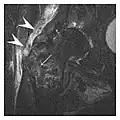

The greater tuberosity of the humerus is also an illustrative location of occult fractures. The osseous injury may follow seizures, glenohumeral dislocation, forced abduction, or direct impaction. They are commonly discovered on MRI in symptomatic patients with suspicion of rotator cuff tear. Coronal images are best suited for detection. They appear as crescentic oblique lines surrounded by a bone marrow edema pattern (Figure 5). The rotator cuff must be inspected since associated ligamentous lesions are common. In the ankle, malleoli and tarsal bones should be checked carefully for any cortical disruptions and radiolucent lines that may reveal a fracture. Awareness of the exact location of the pain will help direct the attention of the interpreter when searching for very subtle signs of fracture (Figure 6).[1]

Figure 13: Partial osseous avulsion of the gluteal muscles at the greater trochanter in a 59-year-old man who presented with the right hip pain without a history of trauma. Lauenstein view and anteroposterior and radiographs (not shown) did not show an obvious fracture line or disruption of bony contours in the acetabulum or the right femoral neck. (a) Coronal T1-weighted MRI displays an incomplete fracture line extending partially from the greater trochanter (arrow). (b) Coronal short tau inversion recovery MRI shows heterogeneous hyperintensity in the same region (arrow) as well as hyperintensity within the gluteus medius and minimus muscles (arrowheads) consistent with tissue edema and hematoma.[1]